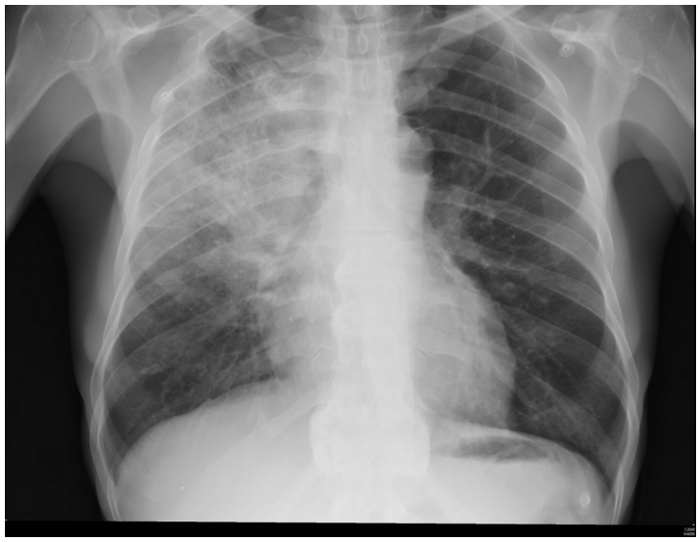

.......Um paciente de setenta anos de idade, com queda do estado geral e inapetência há cerca de três dias, previamente hipertenso e diabético, apresenta-se sonolento e pouco responsivo, com PA de 100 x 60 mmHg, TEC de 4 segundos e FC de 126 bpm. Seus familiares contam que ele tem quadro de tosse produtiva há cerca de uma semana. Exames disponíveis: Hb 14; leucócitos 10.000; plaquetas 200.000; Ur 40; e Cr 1,2. O RX do paciente é mostrado abaixo.

Internet: <https://www.todoestudo.com.br/wp-content/uploads/2018/02/pneumonia.jpg>.

Com base nesse caso hipotético, assinale a alternativa que apresenta a conduta mais adequada.